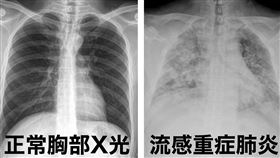

「肺炎人就走了?」醫揭流感1大關鍵差異

女星大S(徐熙媛)因流感併發肺炎在日本逝世,享年48...